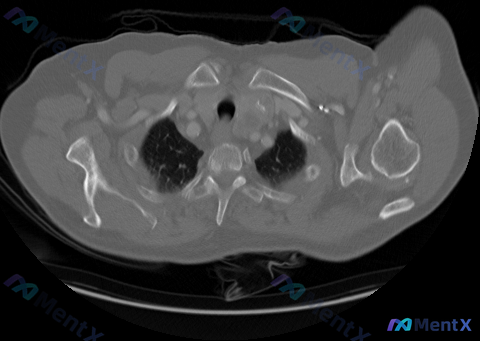

这份图像是胸廓入口及上纵隔区域(主动脉弓上方层面)的横断面:

- 纵隔结构与淋巴结:气管居中、通畅,气管前及左侧间隙(2R/2L/3区)可见多发软组织密度结节,部分有融合成团趋势,密度相对均匀,未见明显粗大钙化或低密度液化坏死;

- 周围间隙:纵隔脂肪间隙因结节存在而模糊、消失,提示受累;

- 其他:大血管分支形态正常,肺尖部可见部分充气肺组织,无明显胸膜增厚或积液。